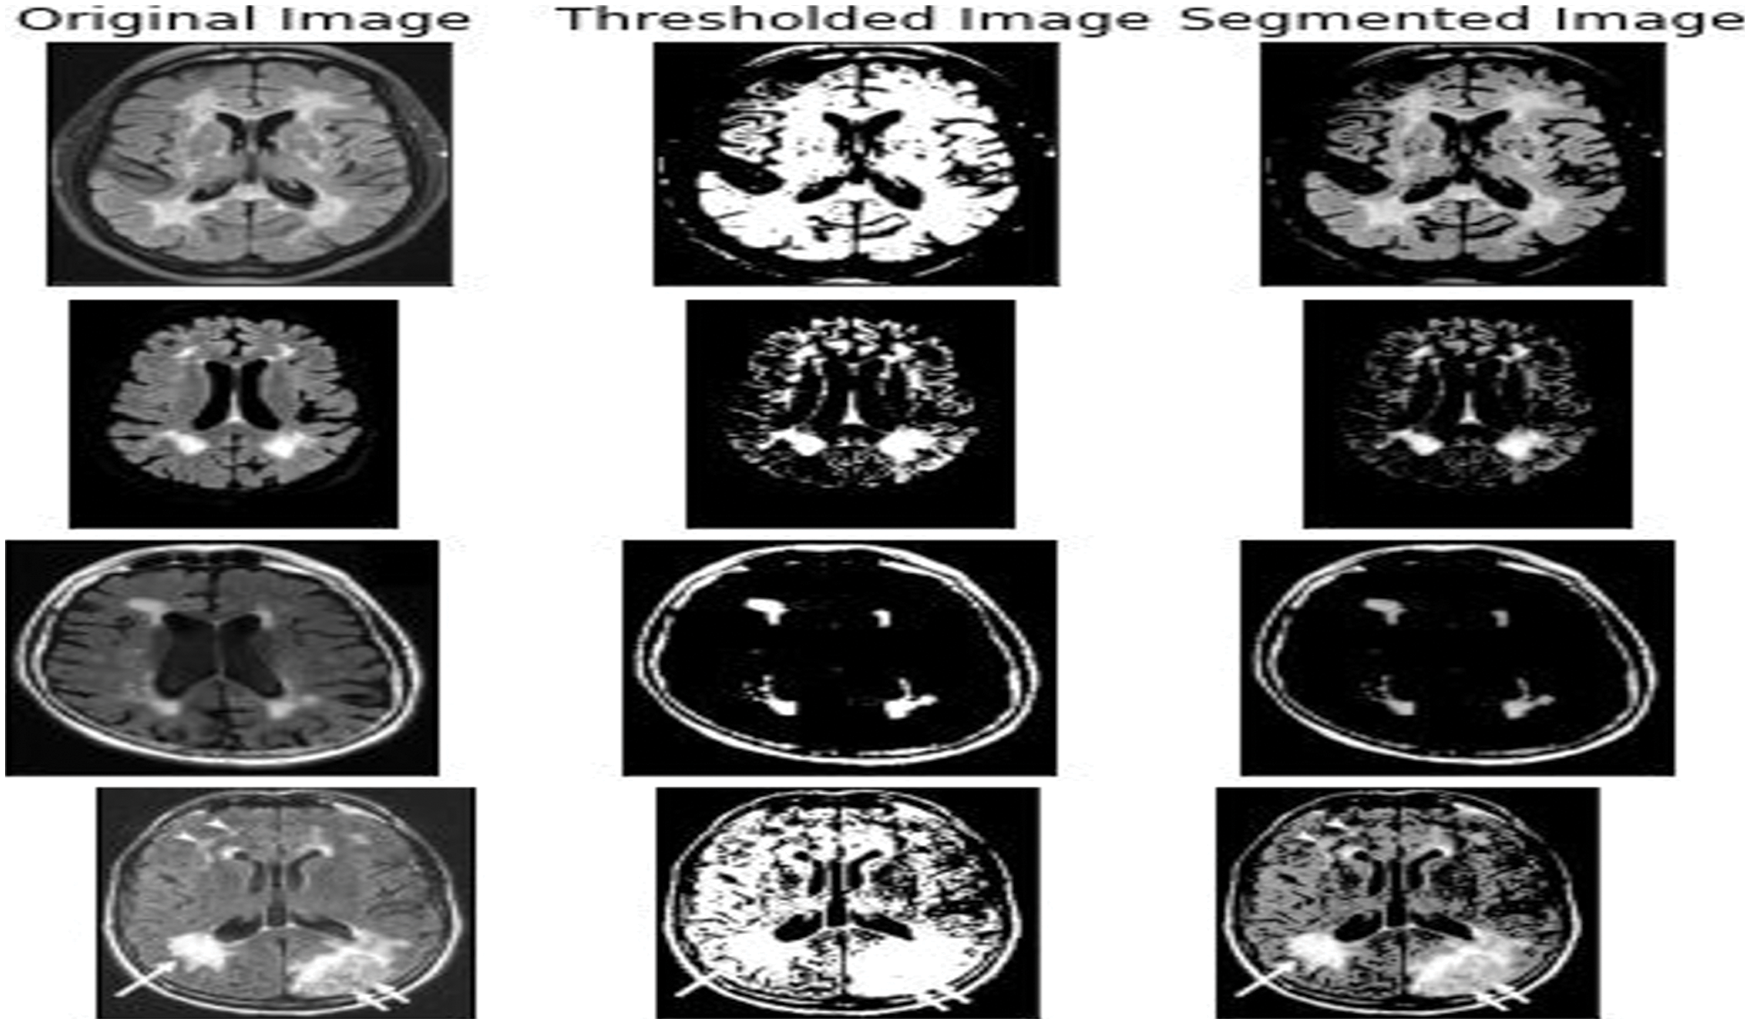

The lesser the threshold, the more homogeneous the segments will be. A larger threshold value will cause a more heterogeneous and generalized segmentation result. Every image is made up of a collective group of pixels values. In image segmentation the task is to classify the image into various segments depending on the classes assigned to the pixel value. Processing the entire image doesn’t serve any fruitful purpose, So segmenting pixels on an apt threshold value helps us in detecting WMH areas that are usually missed out. Thresholding is a type of segmentation where we change the pixels of an image to make the image easier to analyze. The school old methods of thresholding like Otsu’s Thresholding [10], adaptive thresholding, and grab cut thresholding methods were used with the dataset to help gain a better understanding of the optimized threshold value. The drawback of Otsu’s thresholding of WMH was the inability of the method to detect the number of occurrences of the false positives because of the heterogenous nature of the pixels [11] Otsu’s thresholding technique would have been suitable for a bimodal image. The histograms that were displayed for the noisy images fed, did not serve the purpose and the peak of thresholding wasn’t visible enough. Next the adaptive thresholding technique was utilized with multiple thresholds this was apt when dealing with the varying intensities of WMH. But the disadvantage of adaptive thresholding was that the size of the neighborhood had to be large enough to cover sufficient foreground and background pixels, otherwise a poor threshold was chosen. In the case of WMH, the pattern of occurrence is very hazy and hard to identify [12]. The grabcut segmentation worked fairly well but required the ROI to be specified. This study as shown in Fig. 1 helped us gain an insight that deep learning models would be well suited for the automatic detection of features and to increase the accuracy of segmentation and speed.

Figure 1: 2D FLAIR image from the WMH dataset was fed and the basic thresholding methods were performed on it